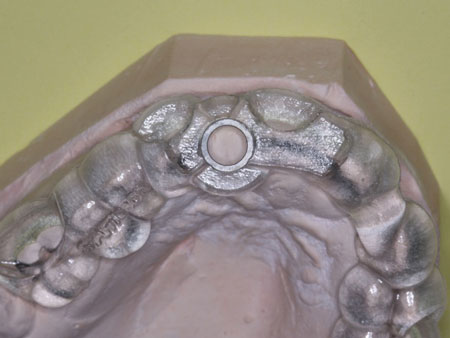

12. The lab will make the guide and send it to you (figures 1 and 2).

Figures 1 and 2:

The lab has made a printed surgical guide for a specific case. The designated drill is easily related to the guide and provides near-perfect placement of the implant.